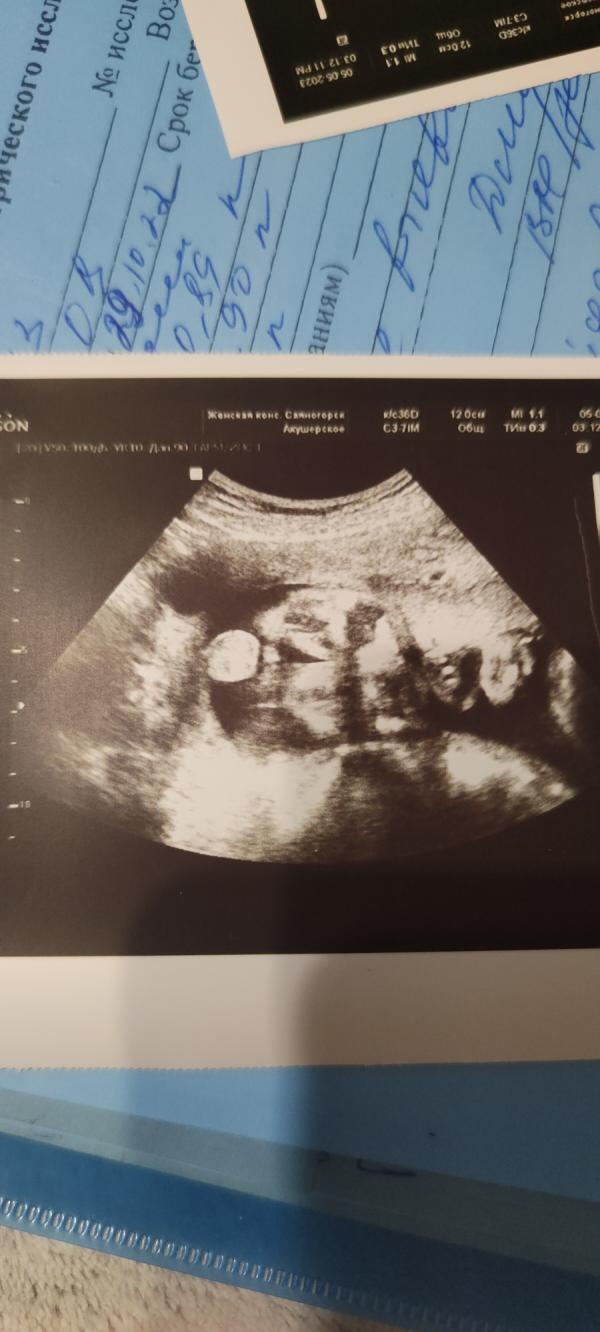

Вот теперь мы на 100% уверены что у нас будет сын. Можно подготавливаться по тихоньку но мне лень🙈🤭 29 мая в декрет, может тогда уйдёт она🤣